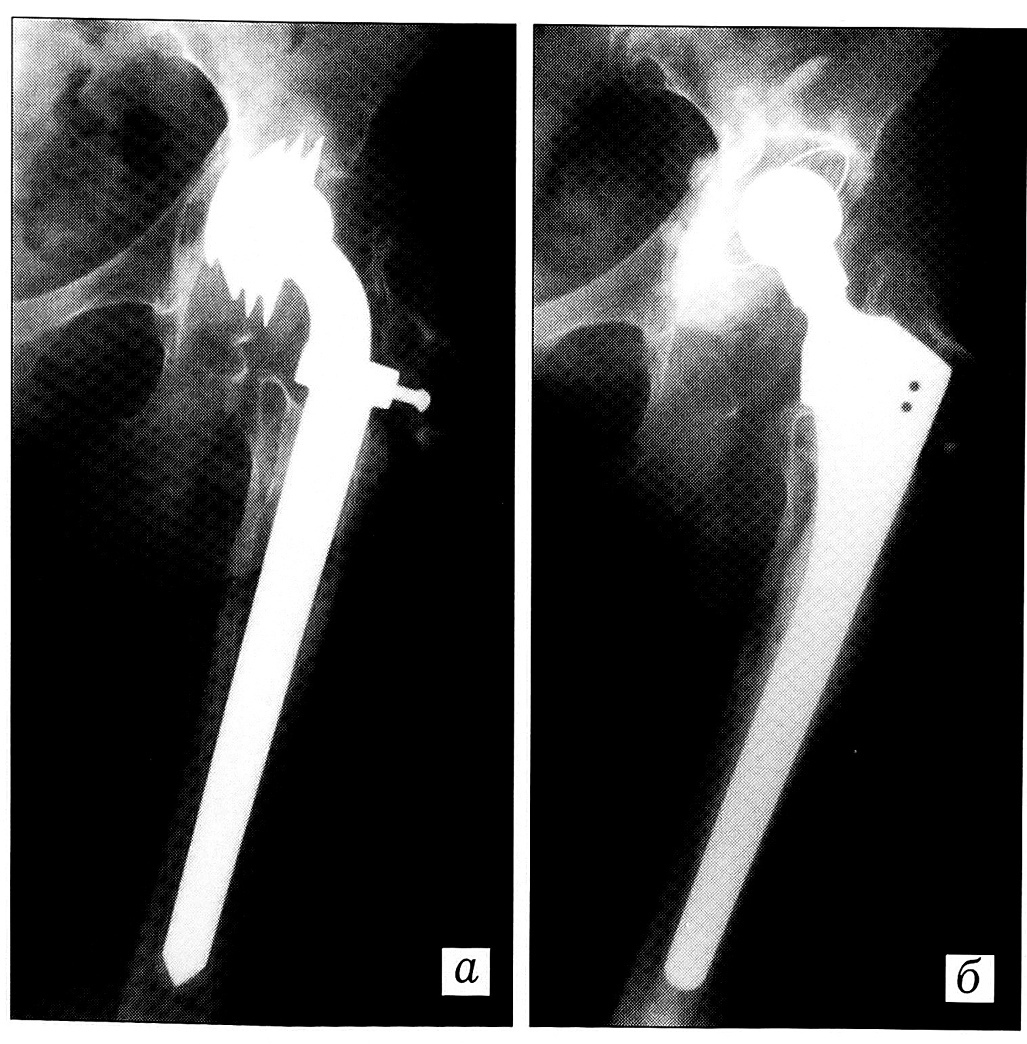

Причины нестабильности эндопротезов. На первом месте среди причин нестабильности остается асептическое расшатывание компонентов. Далее идут износ полиэтиленового вкладыша, перелом имплантата (рис. 1), перелом диафиза бедра, рецидивирующий вывих, глубокая инфекция, ошибки в технике операции. Причиной ранней нестабильности протезов «Компомед» является быстрое изнашивание полиэтиленового вкладыша, сопровождающееся выраженным полиэтиленозом, обширным остеолизом вертлужной впадины и проксимального отдела бедра.

Рис. 1. Рентгенограммы больной 59 лет. а — перелом ножки эндопротеза (Poldi) правого тазобедренного сустава; б — состояние после ревизионного тотального эндопротезирования цементируемым протезом ЭСИ с использованием «скользящей» обширной остеотомии большого вертела и дополнительной фиксацией серкляжными швами.